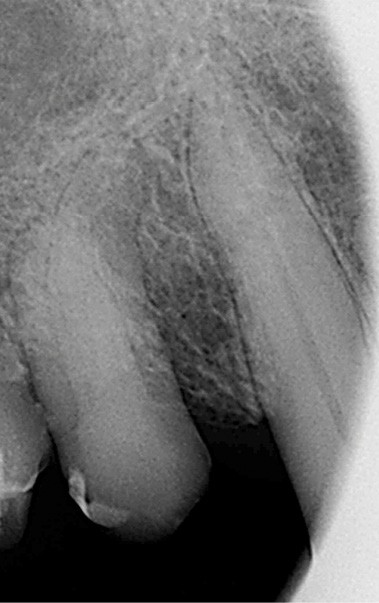

Un patient de 84 ans, en bon état de santé générale, consulte pour la perte de trois couronnes solidarisées métalliques 17, 16 et 15 qui permettaient la rétention d’une PAP à châssis métallique (fig. 1 à 5).

L’examen clinique permet de mettre en exergue, au maxillaire :

– 17, 16 sont à l’état de racines, 15 est déjà préparée et ne présente aucune symptomatologie pulpaire ;

– 13 est intacte ;

– 12 est couronnée et présente une mobilité importante et un épaississement ligamentaire ;

– 11 est couronnée ;

– carie radiculaire importante à la 21 ;

– 22 est couronnée et présente également une carie radiculaire ;

– 13 est très cariée et présente une alvéolyse dépassant le tiers apical de la racine.